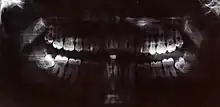

Radiologie dentaire

La radiologie est quotidiennement pratiquée en cabinet dentaire par le chirurgien-dentiste à des fins d'analyse diagnostique ou d'examens complémentaires en odontologie[6].

Le type de cliché radiographique dentaire dépend de l'indication. On distingue :

- la radiographie panoramique, ou orthopantomogramme (OPT) ;

- la radiographie rétro-alvéolaire (periapical view), essentiellement en endodontie ;

- la radiographie rétro-coronaire (bitewing view), essentiellement en odontologie conservatrice ;

- la radiographie occlusale (occlusal view), essentiellement en traumatologie ;

- les clichés radiographiques de la face par tomodensitométrie (Conebeam - Computed Tomography), essentiellement en implantologie ;

- la téléradiographie de la face et des poignets, essentiellement en orthodontie[7].

Le cliché radiographique est réalisé par le chirurgien-dentiste à l'aide d'un film argentique ou d'un capteur numérique intra-buccal ou extra-buccal suivant la nature de l'examen[7].